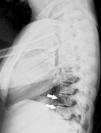

En los estudios radiológicos, además de la marcada esclerosis ósea, llamaba la atención, en la columna, la presencia de líneas paralelas a la cortical de los cuerpos vertebrales que daban lugar a la imagen de un pequeña copia del cuerpo vertebral en su interior, el denominado signo del «hueso dentro de hueso» (figs. 1-3). Este signo era evidente en varios cuerpos vertebrales. No presentaba deformidades morfométricas vertebrales ni calcificación de los ligamentos paraespinales.